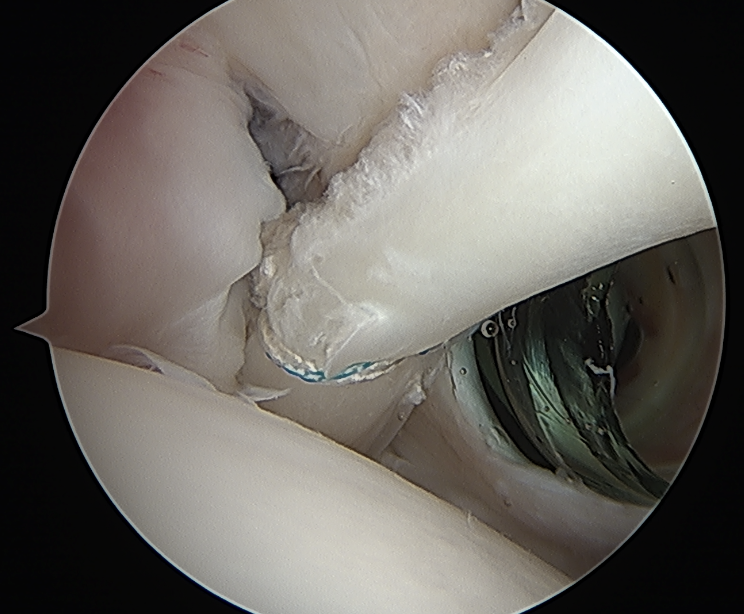

Anchor biceps tendon into bicipital groove